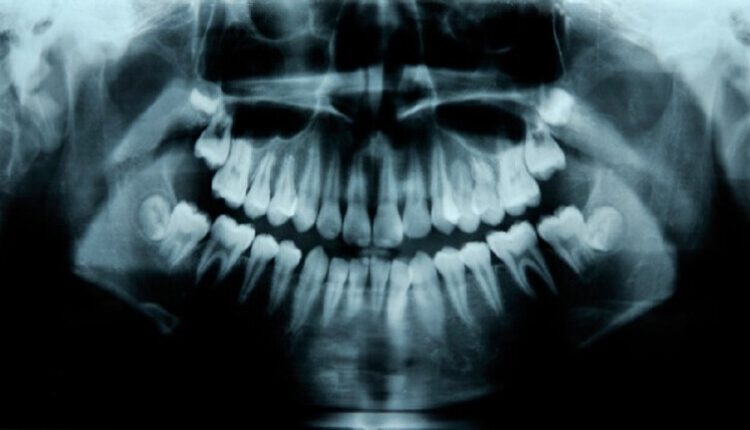

محاكمة طبيب أسنان ووالده بتهمة اقتلاع 580 سنا سليمة

تتواصل في مدينة مرسيليا الفرنسية محاكمة طبيب الأسنان السابق ليونيل ووالده جان كلود جويدج منذ أربعة أسابيع، بتهمة اقتلاع 580 سنا سليمة لأغراض مالية.

والتهمة الموجهة للطبيب هي “التسبب في إعطاب لأهداف مادية” لحوالي 350 مريضا قصدوه في عيادته بالحي الشمالي لمرسيليا للعلاج من ألم في الأسنان.

وقام المتهم ووالده باقتلاع أسنان عشرات المرضى من دون وجه حق، وذلك بهدف عمل أطقم صناعية أو زراعة أسنان لهم، وهي طرق العلاج الأكثر ربحا.

وتقدم محامي الضحايا مارك سيكالدي بقائمة جاء فيها أن المتهمين الاثنين اقتلعا 580 سنا صحيحة من أفواه 55 مريضا من موكليه.

وقال في مرافعته: “لكي تدركوا حجم الضرر فإن هذا الرقم يعني بمجموعه تشويه 20 فما، وحرمانها من الأسنان بالكامل”.

واستنادا إلى نتائج التحقيقات، فإن الطبيب كان يلجأ إلى تعرية السن من الميناء الخارجية بهدف تعريض المريض لحساسية مؤلمة عند تناول المشروبات الساخنة أو الباردة، وبعد ذلك يقنعه بضرورة قلع السن وتركيب جسور، أو زرع أسنان صناعية مرتفعة الكلفة، وفي عدد من الحالات تم تغيير كامل الأسنان.